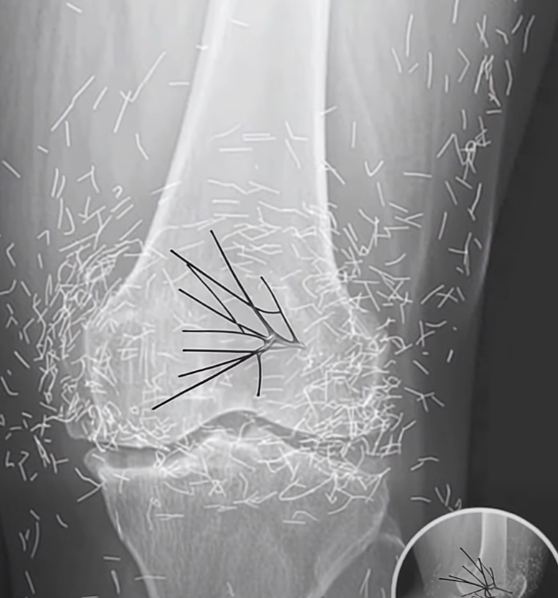

Unexpected Discovery in Woman’s Knee During Routine X-Ray

When a 65-year-old woman in South Korea visited the hospital for what she believed would be routine arthritis tests, she expected a familiar answer about her swollen, painful knees. Instead, doctors uncovered something extraordinary on her X-ray: her joints were filled with hundreds of tiny gold needles. The surprising discovery shed light on a rare practice that few had ever encountered.